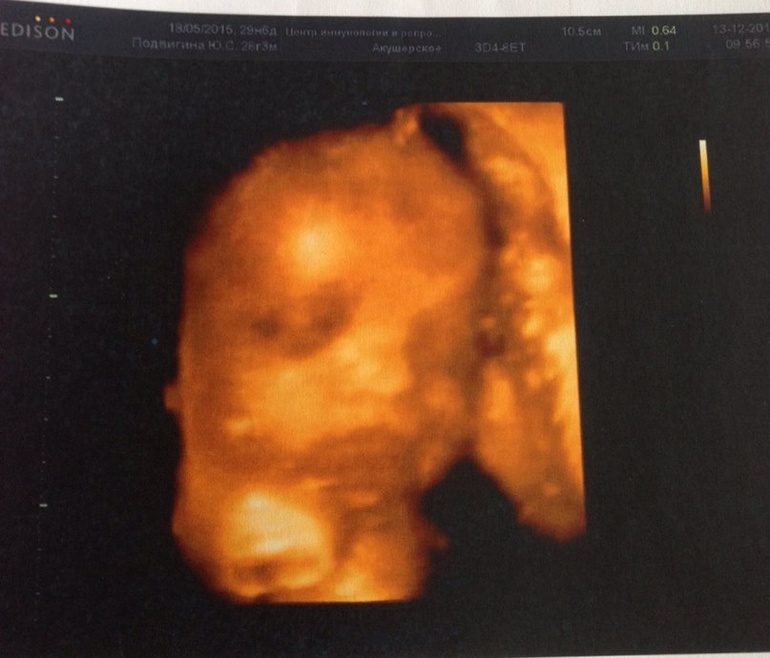

Наше 3D узи в 30 неделек.

По узи ПМП 1560 г, рост нашей малышки 37 см, единственное лежит поперек, но время есть думаю перевернется. Все параметры полностью соответствуют сроку. Ну и наша принцесса